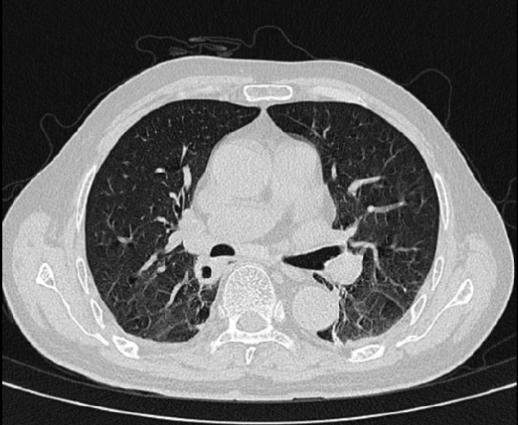

去年冬天,他在自家地里干完农活后,开始出现发热,就去当地医院,查了胸部CT提示肺部炎症,进行了抗菌、抗病毒治疗后,症状却越来越重。

进行了一系列检查后,医生发现老许除了肺里有个空洞结节外,大脑里还长了几个“结节”。

胸部CT提示右肺下叶病灶伴空洞形成